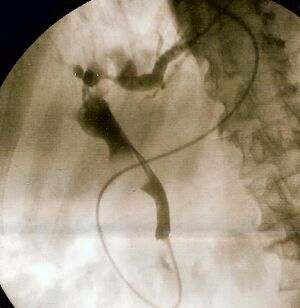

| صورة منظار للاثني عشر لبثق صديد من أمبولة ڤاتر، مما يدل على التهاب الأقنية الصفراوية. | |

The gold standard test for biliary obstruction is still endoscopic retrograde cholangiopancreatography (ERCP). This involves the use of endoscopy (passing a tube through the mouth into the esophagus, stomach and thence to the duodenum) to pass a small cannula into the bile duct. At that point, radiocontrast is injected to opacify the duct, and X-rays are taken to get a visual impression of the biliary system. On the endoscopic image of the ampulla, one can sometimes see a protuberant ampulla from an impacted gallstone in the common bile duct or the frank extrusion of pus from the common bile duct orifice. On the X-ray images (known as cholangiograms), gallstones are visible as non-opacified areas in the contour of the duct. For diagnostic purposes, ERCP has now generally been replaced by MRCP. ERCP is only used first-line in critically ill patients in whom delay for diagnostic tests is not acceptable; however, if the index of suspicion for cholangitis is high, an ERCP is typically done to achieve drainage of the obstructed common bile duct.[1]